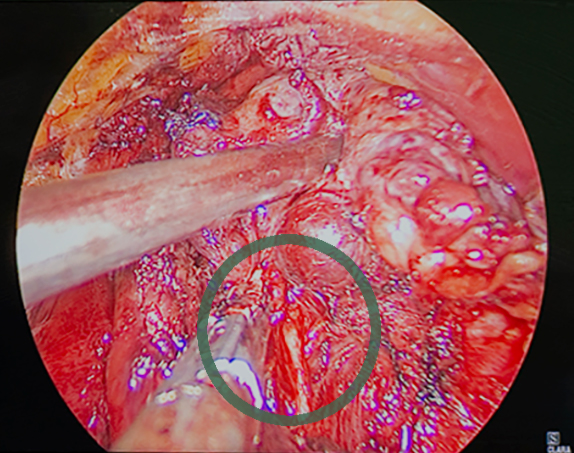

Операция видеоэндохирургическая гемитиреоидэктомия с истмусэктомией справа (удаление одной доли щитовидной железы и ее перешейка) у пациента 40 лет с доброкачественным образованием щитовидной железы проводилась эндоскопическим методом: эндоскопическая техника дает несравнимую с открытыми операциями возможность визуализации всех анатомических структур. В начале операции, приблизившись к нервам, мы проверили «замкнутость цепи»: если нерв отвечает на стимуляцию, на мониторе появляется сигнал, по его амплитуде оценивается степень его травматизации, что позволяет внести коррективы в ход хирургического вмешательства. Так определяют наличие или отсутствие проблем, НЕ связанных с данной операцией. На рис. 2 сигнал от возвратного гортанного нерва. Далее в процессе операции, как я уже отмечал выше, можно в любой момент контролировать сохранность функции нерва.

Визуализация возвратного гортанного нерва Стимуляция гортанного нерва